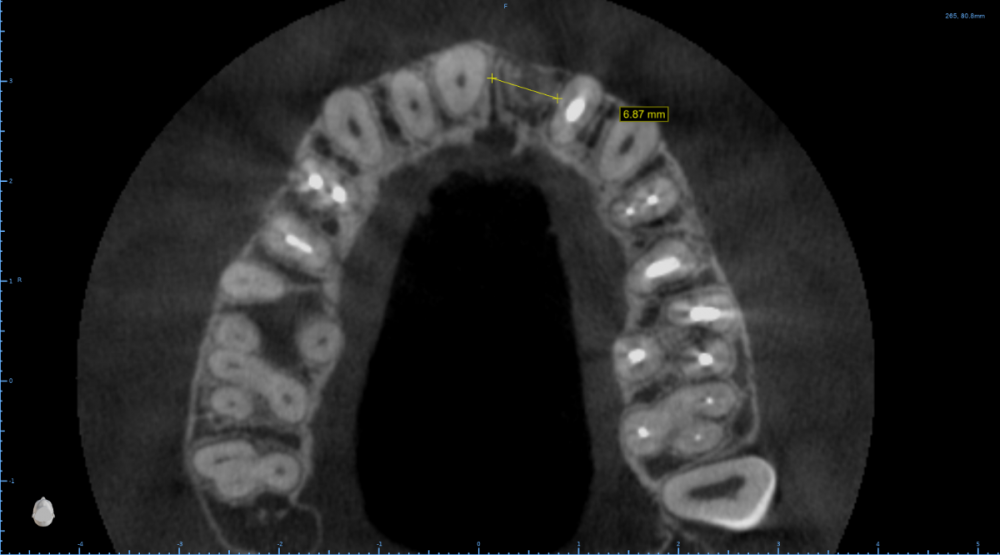

Женька Опубликовано 6 февраля, 2022 Поделиться Опубликовано 6 февраля, 2022 Как это решить максимально просто? Ни НКР ни расщепления ранее не делал (нормальную НКР, с пинами, ауто+ксено и тд). Так что вариант "что получается лучше" не подходит. Какие ещё срезы нужны для планирования? Пациентка маленькая, худощавого телосложения. На данный момент ходит с "бабочкой". Сам склоняюсь к НКР, тк это в моей голове проще реализуемо. Может есть какие-то другие варианты? Ссылка на комментарий

Irouil Опубликовано 6 февраля, 2022 Поделиться Опубликовано 6 февраля, 2022 Анкилос 3.5 с андерпрепом и небольшой компрессией, заглубить Ссылка на комментарий

Irouil Опубликовано 6 февраля, 2022 Поделиться Опубликовано 6 февраля, 2022 (изменено) 25 минут назад, Женька сказал: @Irouil в наличии только Дентиумы (ну возможно ещё мис получится заставить начальника закупить) Дентиум 3.6 по такому же принципу 25 минут назад, Женька сказал: но всех ведь не будешь протоколить?) Всех будешь Изменено 6 февраля, 2022 пользователем Irouil Ссылка на комментарий

Женька Опубликовано 7 февраля, 2022 Автор Поделиться Опубликовано 7 февраля, 2022 @TIGER ну как при моделировании шаблона, да? @Irouil получается типа расширение гребня имплантатом, вы об этом? и более нёбное позиционирование Ссылка на комментарий

Irouil Опубликовано 7 февраля, 2022 Поделиться Опубликовано 7 февраля, 2022 2 часа назад, Женька сказал: получается типа расширение гребня имплантатом, вы об этом? и более нёбное позиционирование Пилотное сверло 2.0 + спредер 2/3, к примеру Ссылка на комментарий

pit Опубликовано 8 февраля, 2022 Поделиться Опубликовано 8 февраля, 2022 (изменено) 06.02.2022 в 22:25, Женька сказал: 4 часа назад, Doctor Vlad сказал: 06.02.2022 в 22:25, Женька сказал: @pit увы, фоток улыбки нет, как и воспоминаний... (надо как-то иначе видимо строить первичную консультацию, но всех ведь не будешь протоколить?) тем не менее какие варианты при высокой и низкой? При низкой линии улыбки узкий имплант в небную позицию и все( если не хочется заморачиваться) При высокой тоже в более небную позицию+ растянуть кость (винтовыми остеотомами например) + ССТ+ временная коронка Изменено 8 февраля, 2022 пользователем pit Ссылка на комментарий